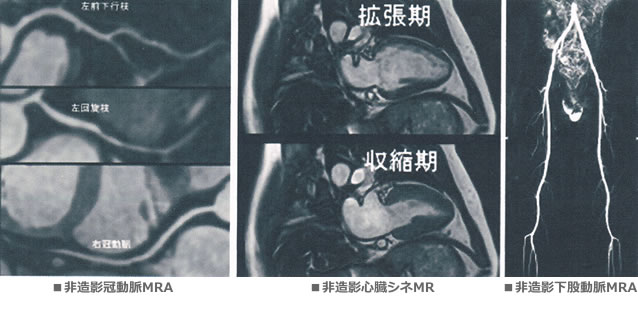

MRIでは造影剤を使わずに冠動脈を含む全身の血管を撮影できます。

造影剤(Gd)と薬物(ATP)を使えば心筋の血流状態を詳しく知ることができます。